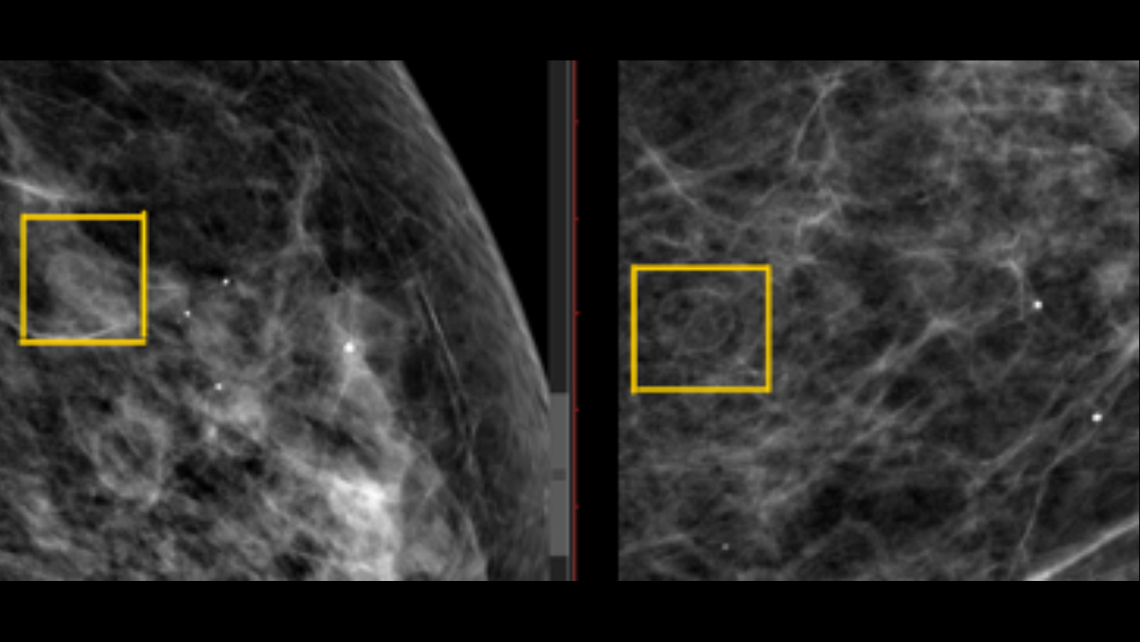

Se trata de paciente femenina de 57 años de edad, sin antecedentes pertinentes, que consulta por presentar dolor a nivel del seno izquierdo, motivo por el cual se solicita evaluación con estudio de mamografía, evidenciándose lo siguiente:

Mamas con moderada cantidad de tejido fibroglandular distribuido predominantemente en cuadrantes supero-externos, con patrón ACR-B, observándose en el cuadrante supero-interno de la mama izquierda imagen redondeada, de menor densidad con respecto a tejido mamario, paredes discretamente calcificada, que mide 9 x 6.5mm, sugestivo de quiste oleoso.